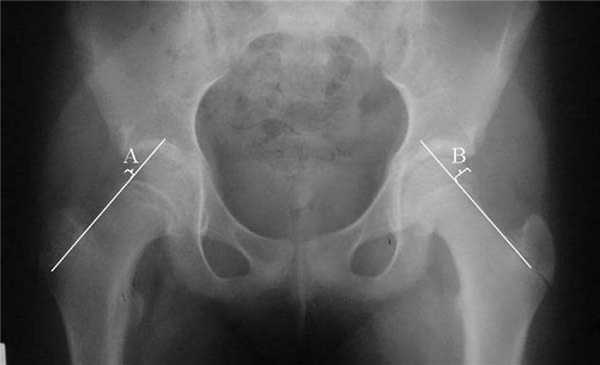

Выделяют 5 последовательных рентгенологических этапов развития эпифизеолиза головки бедра:

- 1 стадия - предсоскальзывания или предлистеза. Характеризуется патологическими изменениями ростковых зон эпифиза головки, апофизов большого и малого вертелов, гиперостозом верхней части шейки бедра.

- 2 стадия - смещения до предела толерантности сустава. Отмечается хроническое течение, сопровождающееся смещением эпифиза кзади до 30°, уменьшением эпицервикального угла до 60°.

- 3 стадия - смещения за пределы толерантности сустава. Хроническое смещение прогрессирует, головка смещается кзади на 30° и более, эпицервикальный угол составляет менее 60°, шеечно-диафизарный - менее 120°.

- 4 стадия - острого смещения эпифиза. Головка полностью отделяется от шейки, угол между диафизом и шейкой составляет 90-75°, на снимках определяется линия перелома, ранние признаки сращения между шейкой и головкой с сохранением смещения.

- 5 стадия - остаточных деформаций. Верхние отделы бедренной кости полностью срастаются в порочном положении.

Поражение головки бедра диагностируется травматологами-ортопедами на основании жалоб, результатов объективного обследования и визуализационных методик. Основным методом обследования является рентгенография тазобедренного сустава. Процедура выполняется в 2 проекциях, наиболее информативна боковая проекция. Изменения зависят от стадии заболевания.

Сначала ростковый хрящ на рентгеновских снимках расширяется, шейка становится слоисто-пятнистой из-за чередования участков остеосклероза и остеопороза. Затем обнаруживается прогрессирующее смещение головки, после этого просматривается линия перелома. На заключительной стадии выявляются признаки консолидации перелома, ремоделирование шейки бедра, сужение суставной щели.